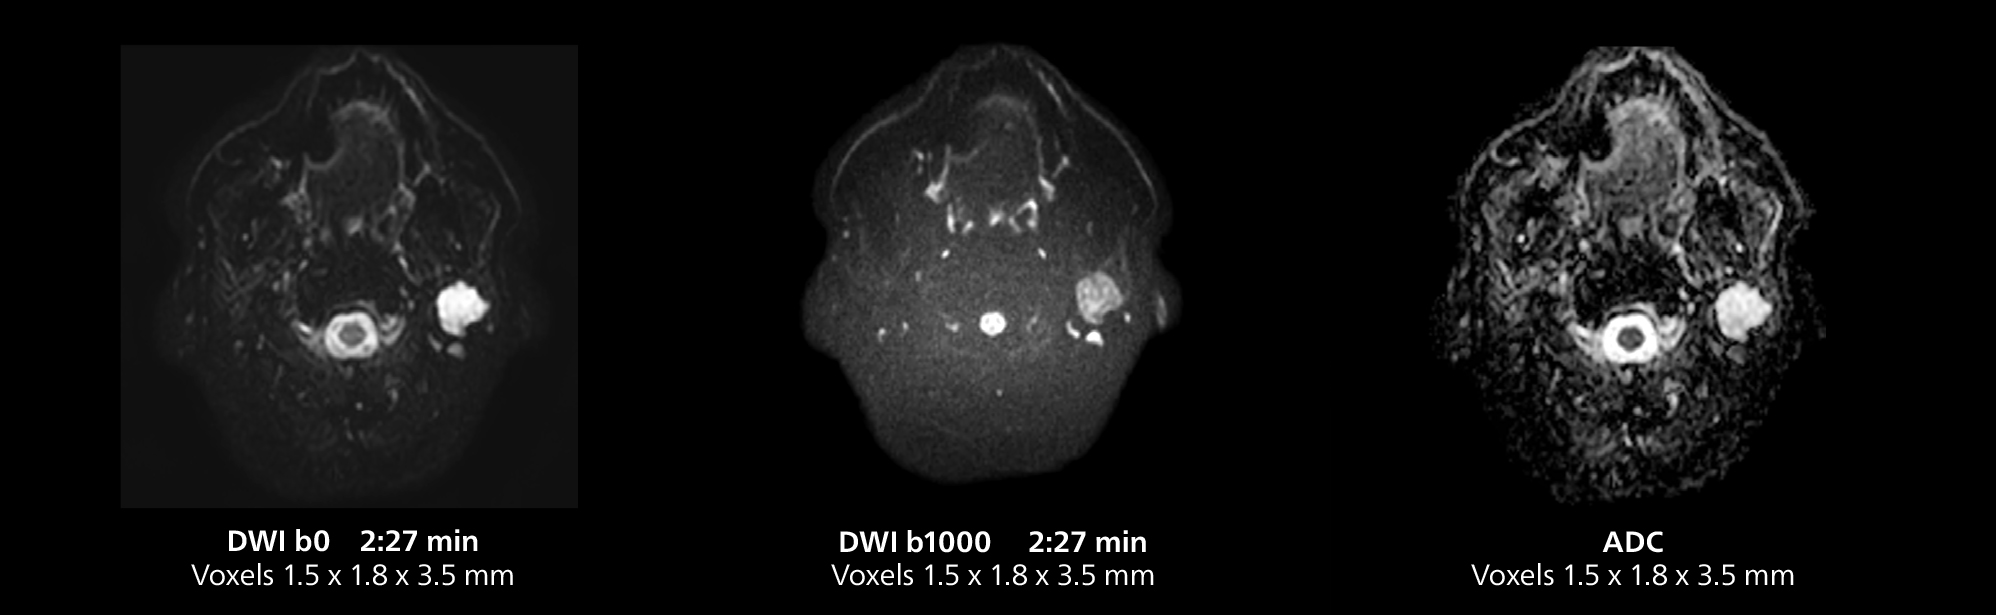

Salivary gland imaging on MR 5300

This MRI case illustrates imaging of salivary gland abnormalities with different sequences. Compressed SENSE allows to accelerate scanning while maintaining high quality. With mDIXON XD, different contrast types can be obtained from scanning one sequence.

Salivary gland imaging on MR 5300

This MRI case illustrates imaging of salivary gland abnormalities with different sequences. Compressed SENSE allows to accelerate scanning while maintaining high quality. With mDIXON XD, different contrast types can be obtained from scanning one sequence.